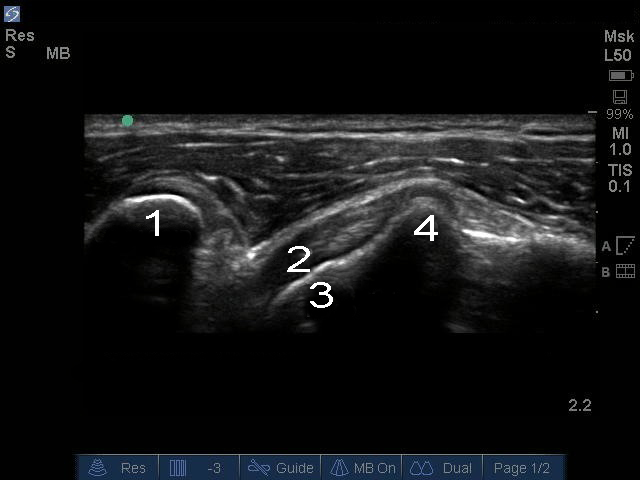

肩甲下筋および烏口骨プロセスの画像

肩前部肩甲下筋腱

烏口骨

肩甲下筋

上腕骨頭

小結節